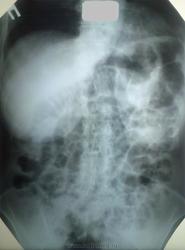

Спасибо за помощь...я тоже данных за грыжу не нашел....да и график пищеварения в целом не нарушен. Вот снимок через 24 часа.

Думаю, что основными причинами есть мезентериально-алиментарные факторы (т.е. - как нарушение кровоснабжения кишечника, так и самого процесса пищеварения).

ИМХО: всё-таки остаётся впечатление с учётом жалоб, что это аэрофагия. Посоветовал, бы проконсултировать пациентку психиатром.

Вот, вот! И я про то же. См. пост №5. Воздух по ЖКТ распределён равномерно и движется сверху вниз от желудка. Аэрофагия для нас – патология функциональная, однако невролог или психиатр могут найти и органическое поражение в своём хозяйстве.